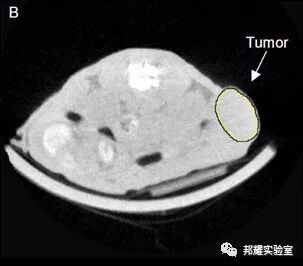

- 有的。如一种micro-CT造影技术可以很精准的计算肿瘤体积。可连续动态地观测到肿瘤在小鼠体内的分布,所占体积的大小和肿瘤的生长变化的情况,操作比较简单,但价格非常昂贵。当然若你有这个条件,这确实是个不错的选择。如下图为micro-CT的扫描结果。

micro-CT的扫描的肿瘤块[5]